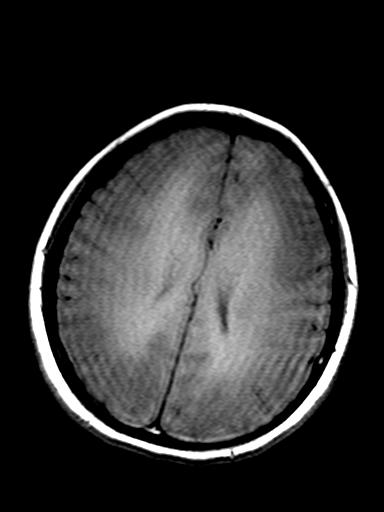

发热、头痛伴精神异常1周

较对称性脑白质异常信号,深部白质t2明显低信号(铁质沉积过多?)

考虑脑白质病变,请结合临床病史及实验室检查进一步分析。